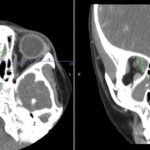

Granulomatosis with polyangiitis (GPA) was first described in the British Medical Journal in 1897 by Scottish otolaryngologist Peter McBride.1 GPA is a relatively rare, systemic necrotizing vasculitis that can make diagnosis challenging. The incidence has been estimated anywhere between two and 12 cases per million.2 GPA mainly affects adults between the ages of 45 and…